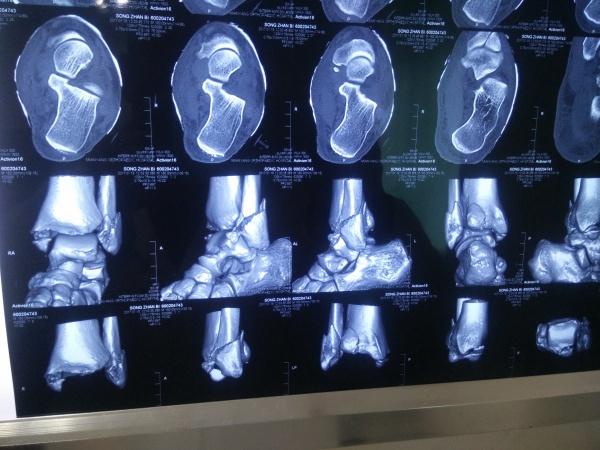

左三踝骨折手术治疗

患者女,外伤后左踝关节活动受限1小时入院,

入院后查体:左踝关节肿胀,活动受限,行DR及左踝关节CT检查,如下图,手术待肿胀消退后行手术治疗,目前愈合良好,请问问各位老师,好久可以下地呀, 下胫腓联合镙钉3个月取呀,